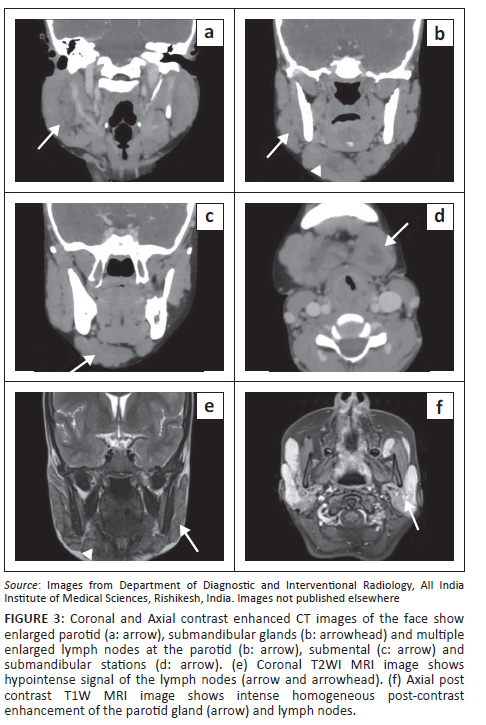

A contrast-enhanced (CE) CT scan of the face and neck (Philips Ingenuity Core 64 slice CT) was performed. Homogeneously enhancing soft tissue masses were seen in the preseptal regions of the eyelids (Figure 2c). Multiple enlarged homogeneously enhancing bilateral cervical and parotid lymph nodes were seen (Figure 3a-d).

Assessing for the disease extent in the face and orbit and for any intracranial involvement, contrast enhanced MRI of the face, orbit and brain (Siemens Magnetom Aera 1.5 Tesla MRI, Germany) was acquired. The enlarged lymph nodes and salivary glands showed T2W hypointense signal and homogeneous post-contrast enhancement (Figure 3e, f). Homogeneously enhancing soft tissue masses were seen in the preseptal regions of the upper eyelids. The masses were hypointense on T1-weighted (T1WI) and T2-weighted (T2WI) sequences. No diffusion restriction was seen. There was extension into the extraconal compartment of the orbits, with abutment of the superior and lateral recti bilaterally. No intraconal or intracranial extension was seen. Both lacrimal glands were bulky showing T2W hypointense signal and homogeneous post-contrast enhancement (Figure 4).